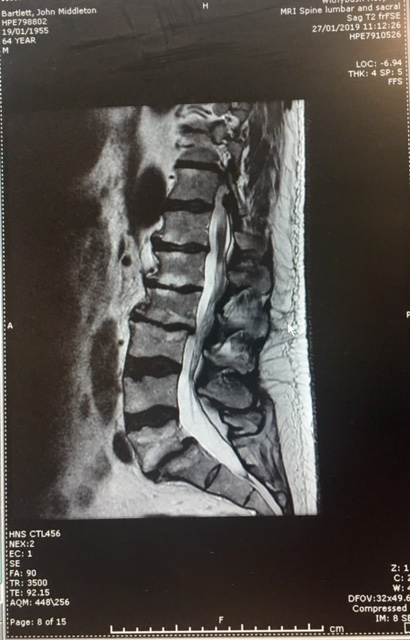

2) In 2023 the CCRC also accepted new MRI scans[63][64]detailing multiple spinal fractures with two broken vertebrae, one having being knocked forward in my lower spine by a quarter of an inch, flattening and severely narrowing the exiting nerves to my right leg, causing a Spondylolisthesis at level L5 S1. These scans proved my injuries were caused by a serious traumatic impact, consistent with my 1988 horse riding accident and evidence the Spinal Surgeon had attempted to tell the Jury[65]